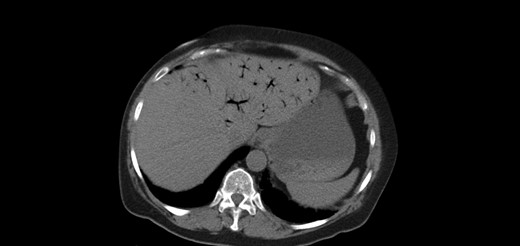

One year later, the patient was brought to the emergency department by her family for altered mental status. They reported 2 days of abnormal behavior and confusion culminating in an episode of bowel incontinence. The patient had difficulty following commands and was complaining of abdominal pain. Initial workup showed tachycardia, hypotension, leukocytosis and elevated creatinine which was treated per sepsis protocol. Her toxicology screen was positive for cocaine. Serum lactate was also elevated. CT brain without contrast showed no acute intracranial process. CT without contrast of the abdomen and pelvis, shown in Figs 3 and 4 , revealed dilated small bowel with gas in the bowel wall. Emergent damage control surgery was performed. There were no signs of gastrointestinal perforation but two segments of necrotic small bowel, 5 feet in total, were removed and the abdomen was sealed with Abthera. Two days later, her abdomen was re-explored and another 40 cm of non-viable small bowel was removed, leaving her with two small bowel anastomosis. Her abdomen was re-explored and closed after another 2 days. She was successfully weaned off the ventilator and continued to improve with supportive care. Final pathology examination revealed extensive necrosis with acute inflammation impacting the serosa at points in the small bowel.

Extensive pneumatosis of the small bowel during the second admission. Approximately 5 feet of ischemic bowel resected.